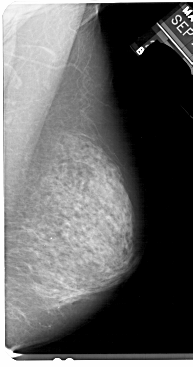

A_1125_1.LEFT_MLO

LEFT_MLO LINES 5491 PIXELS_PER_LINE 3046 BITS_PER_PIXEL 12 RESOLUTION 43.5 OVERLAY

FILE: A_1125_1.LEFT_MLO.OVERLAY

TOTAL_ABNORMALITIES 1

ABNORMALITY 1

LESION_TYPE CALCIFICATION TYPE PLEOMORPHIC DISTRIBUTION SEGMENTAL

ASSESSMENT 4

SUBTLETY 5

PATHOLOGY MALIGNANT

TOTAL_OUTLINES 1

BOUNDARY